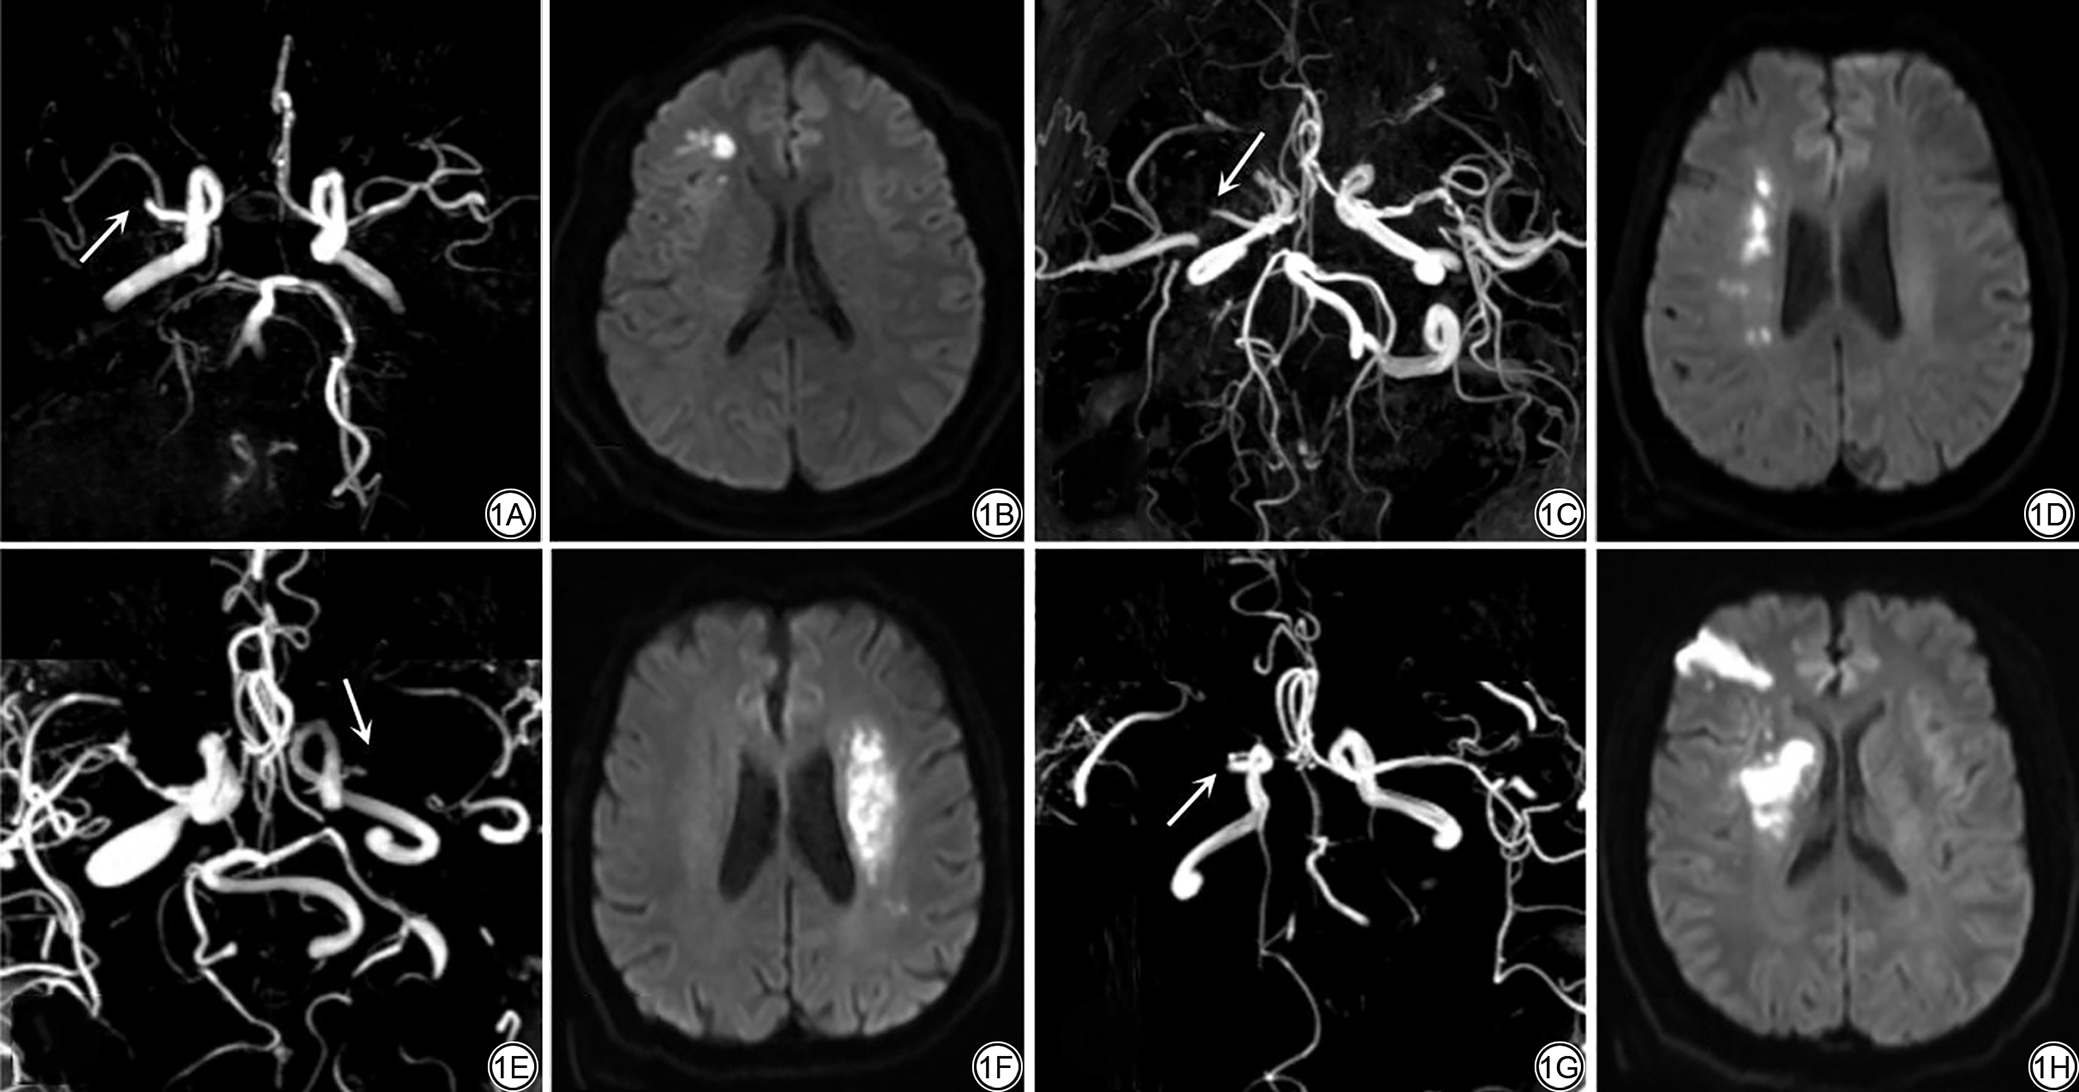

WI多见于50岁以上患者,临床症状包括单侧肢体运动障碍、视野缺失、言语不清和面部下垂等,晕厥、非旋转性头晕和局灶性癫痫样发作症状可能提示WI[5]。包括皮质型与皮质下型WI两个亚型(图1),弥散加权成像(diffusion-weighted imaging, DWI)是检测WI的重要手段[5, 51]。皮质型WI约占40%,病灶分布于大脑前动脉(anterior cerebral artery, ACA)/MCA和MCA/大脑后动脉(posterior cerebral artery, PCA)的供血交界区,病灶位于皮质和皮质下区,可呈三角形或楔形,约2/3表现为皮层小梗死;皮质下型WI主要发生于豆纹动脉或脉络膜动脉与ACA、MCA的交界区,分布于放射冠及半卵圆中心的深部白质区,“串珠状”病灶是其典型表现[52]。幕下WI相对少见,主要见于小脑前下动脉及上动脉交界或脑干基底动脉旁正中分支与小脑动脉供血区域之间[53, 54]

图1  分水岭梗死(WI)弥散加权成像(DWI)及磁共振血管造影(MRA)表现。1A~1B:男,53岁。1A:MRA示右侧大脑中动脉M1段闭塞(箭);1B:右侧额叶皮质型WI。1C~1D:男,60岁。1C:MRA示右侧大脑中动脉M1段闭塞(箭);1D:DWI示右侧放射冠区“串珠状”皮质下型WI。1E~1F:男,70岁。1E:MRA示左侧大脑中动脉M1段闭塞(箭);1F:DWI示左侧放射冠区皮质下型WI。1G~1H:男,52岁。1G:MRA示右侧大脑中动脉M1段闭塞(箭);1H:DWI示右侧混合型WI。

Fig. 1  Diffusion-weighted imaging (DWI) and magnetic resonance angiography (MRA) findings in watershed infarcts (WI). 1A to 1B: A 53-year-old man. Right MCA-M1 occlusion (arrow, 1A) with cortical WI in the right frontal lobe (1B). 1C to 1D: A 60-year-old man. Right MCA-M1 occlusion (arrow, 1C) and “rosary-like” subcortical WI in the right corona radiata (1D). 1E to 1F: A 70-year-old man. Left MCA-M1 occlusion (arrow, 1E) with subcortical WI in the left corona radiata (1F). 1G to 1H: A 52-year-old man. Right MCA-M1 occlusion (arrow, 1G) and mixed-type WI on the right side (1H).